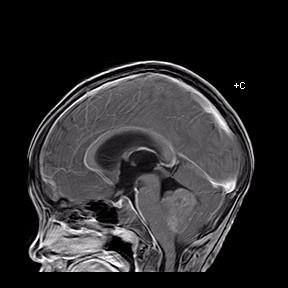

查体见四肢肌力V级,肌张力稍降低,腱反射减弱.生理反射存在,病理征未引出.闭目难立征(+),小脑共济失调征(+)。 头部MR所见:第四脑室内见一团块状稍长T1、稍长T2信号影,病灶大小约 48X33mm,病灶充满第四脑室,且向左侧桥臂侵犯,达左侧硬脑膜,病灶信号不均匀,其内可见点片状长T1、长T2囊性信号,DWI示未见明显异常受限,脑室系统明显扩张,增强扫描病灶呈轻度不均匀强化。双侧侧脑室周围白质见条状FLAIR高信号,边界不清。脑沟、脑裂变窄,中线结构居中。颅骨未见明确骨质破坏。左侧上颌窦、筛窦粘膜增厚。矢状位示垂体形态、信号未见明显异常。